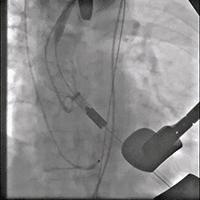

主动脉根部造影

18 mm球囊预扩张

输送系统到位

瓣膜交界对齐释放

22 mm球囊后扩

最终造影